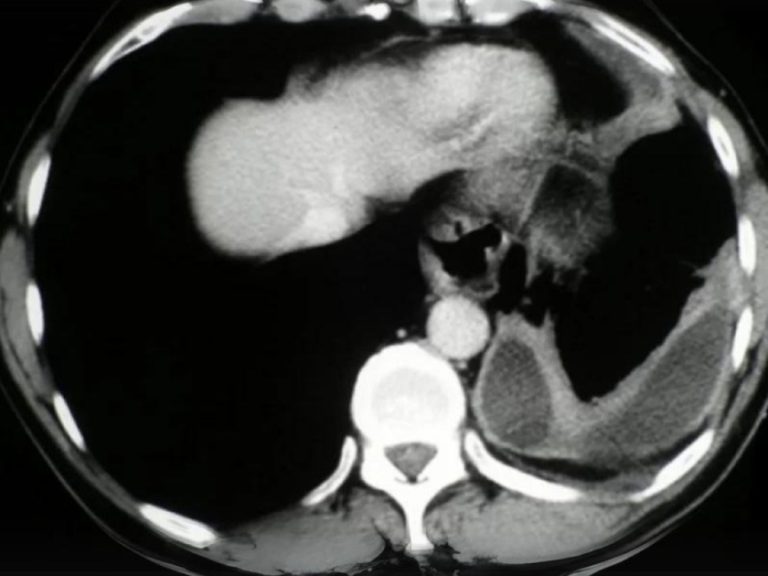

La cirugía toracoscópica asistida por video (VATS) es una técnica quirúrgica mínimamente invasiva que se usa para diagnosticar y tratar problemas en el pecho. El toracoscopio transmite imágenes del interior de su pecho a un monitor de video, lo que guía al cirujano en la realización del procedimiento.

Cirugía Torácica Mínimamente Invasiva

La cirugía torácica mínimamente invasiva, también conocida como cirugía videoasistida (VATS), es una técnica quirúrgica avanzada